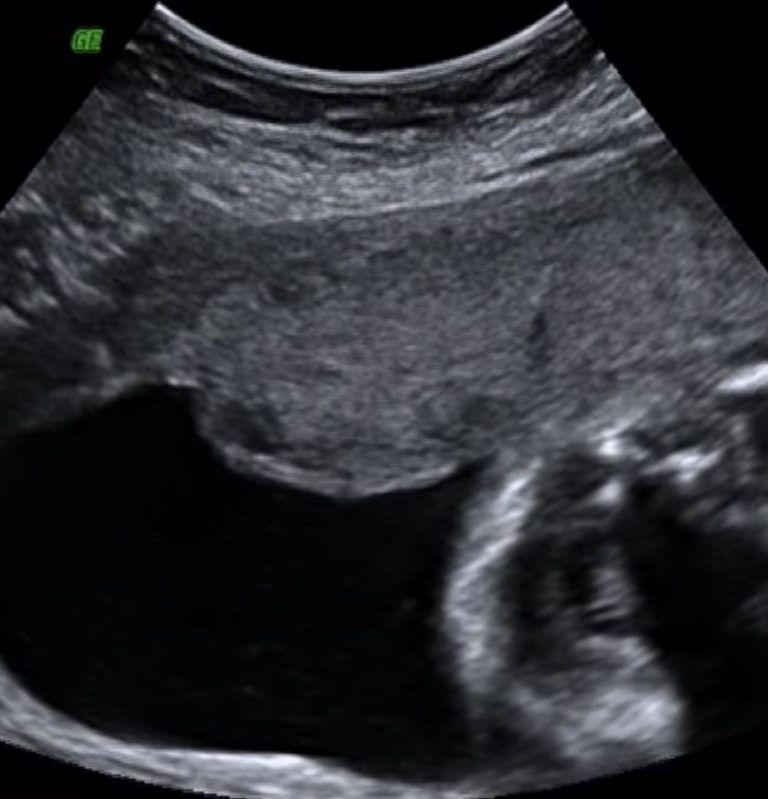

+ רישומי המוניטור כהוכחה לעיכוב בהחלטה על יילוד

מה ניתן לזהות ברישומי המוניטור בזמן אמת

רישומי המוניטור מהווים לעיתים הראיה המרכזית בתביעות רשלנות רפואית בלידה. הם מתעדים באופן רציף את קצב לב העובר ואת תגובתו למצבי לחץ ומצוקה.

לא אחת, סימני מצוקה הופיעו במוניטור בשלב מוקדם, אך לא הובילו לקבלת החלטה בזמן על יילוד. גם בהיעדר סימן קליני דרמטי, המוניטור עצמו עשוי להתריע על החמרה.

- ● טכיקרדיה עוברית מתמשכת

- ● האטות חוזרות או ממושכות בקצב הלב

- ● דפוסי מוניטור שאינם תקינים

- ● שינוי חד בהתנהגות קצב הלב העוברי

בחינה משפטית של רישומי המוניטור, בצירוף יתר התיעוד הרפואי, מאפשרת להראות כי סימני המצוקה הופיעו בפועל. כאשר הצוות לא פירש אותם כראוי או לא פעל בעקבותיהם בזמן, מתגבשת תשתית לטענה של עיכוב בלתי מוצדק בהחלטה על יילוד, לרבות דחייה בביצוע ניתוח קיסרי.